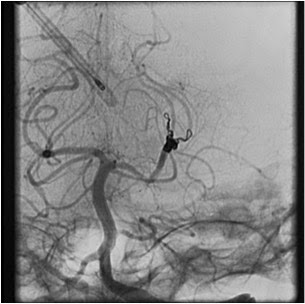

La evolución del paciente es tórpida con deterioro  cognitivo progresivo por lo que se realiza  Angiografía que aprecia:

En la trifurcación de P2 izquierda se observa un aneurisma fusiforme compatible con diagnostico de aneurisma micótico. En la rama inferior (arteria calcarina) se observa un segmento con la pared alterada que también podría estar afectado

Se procede entonces a tratamiento endovascular con cierre de la arteria cerebral media posterior a dicho nivel. En segundo tiempo se realizó embolización de aneurisma y angioplastia de CID